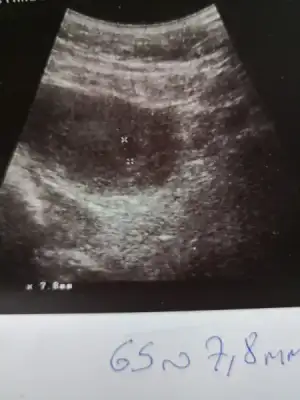

Kimler kimler yazdı?Sağlıklı olsunda bellide olmaz.canim kesede belli oluyoKızlar benimde 14 gün 792 çıktı .

Benim 6. Haftaya girdi acaba keseler görünür mü kalp sesi duyulur mj?Bilmiyorum ki bende merak ettiğim için sordum acaba bugün baktıracak var öı diye bende çarşamba gidicem inşallah

Benim gözüktü kese ama bebek gözükmedi onun için erken dediBenim 6. Haftaya girdi acaba keseler görünür mü kalp sesi duyulur mj?

Senin kaçıncı haftaydı?Benim gözüktü kese ama bebek gözükmedi onun için erken dedi

5+3 deyim benSenin kaçıncı haftaydı?

Ya off acaba benim keseler ne alemde merak etmemek elde değil. Kese varsa bebek nerde acaba o neden görünmedi5+3 deyim ben

Gerçi buranın ultrason cihazı çook kötüydü kesenin bile gözükmesi mucize bakdanoza